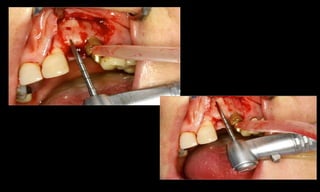

Baixo potencial para perda óssea marginal

(Tenenbaum et al. Impl Dent, 2003);

Resultados estéticos periimplantares otimizados

(Abboud, M. IJOMI, 2005).